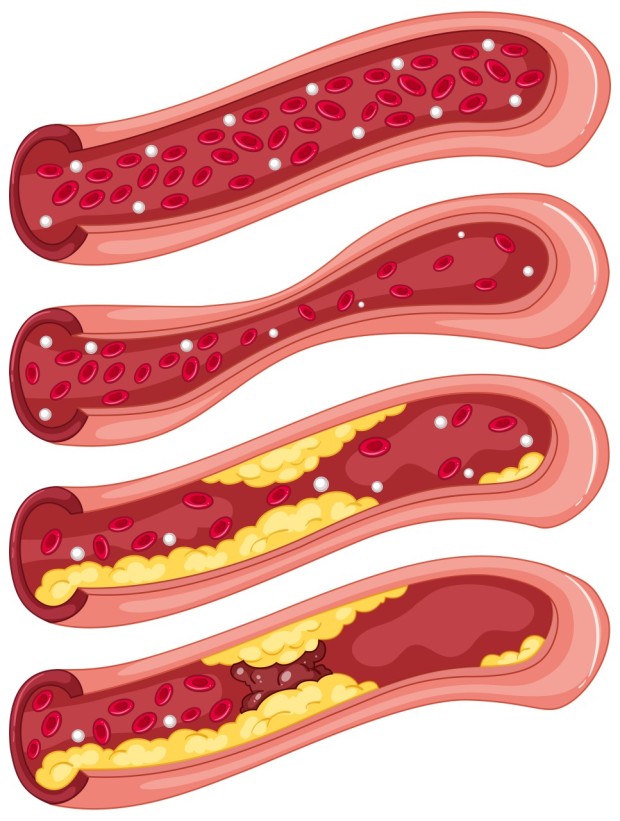

고지혈증 증상 2. 혈액검사에서 LDL 콜레스테롤 수치 상승

눈에 보이지 않지만 가장 정확한 증상입니다.

LDL(나쁜 콜레스테롤) 수치가 높게 나오면

동맥벽에 기름때가 쌓여 혈관이 좁아지고 탄력을 잃게 됩니다.3. 피로감과 무기력증

고지혈증 증상 10. 심근경색 또는 뇌졸중 위험 증가

고지혈증을 방치하면, 혈관 속에 플라크가 쌓이고,

이것이 혈전을 만들어 혈관을 막아버릴 수 있어요.

결과적으로 심근경색, 뇌졸중(뇌경색) 같은 치명적 질환으로 이어질 수 있습니다.

이런 상태에 이르기 전에 관리가 꼭 필요합니다.고지혈증 주의사항